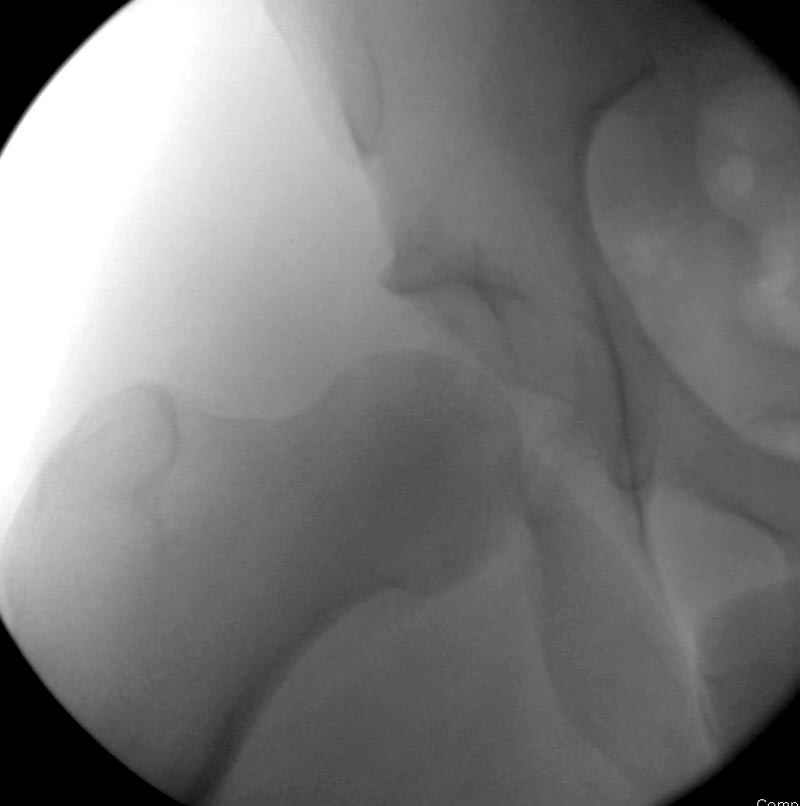

5:24 Рентгенограмма таза, вызывают врача ортопеда (снимок N1), его диагноз: закрытый переломо-вывих правого тазабедренного сустава, получает добро на закрытую репозицию в приемном отделении

5:38 Дважды неудачная попытка закрытой репозиции в приемном отделении

N 2

6:20 ответстенный врач принимает решение о репозиции в условиях операционной, предупреждаются родственники и больной, что при неудачной закрытой репозиции, о возможности открытой репозиции и фиксации задней стенки вертлужной впадины.

7:30 начало операции, больной на спине, попытка репозиции после анестезии N3, укладка больного на боку, доступ Kocher- Langenbeck, состояние седалищнего нерва около 2.5см кровоподтек, через joistick головка бедра приподнята, освобовождение сустава, фрагмент заднего края более 3х4 см репонирован на свое место. После промывания

Интраоперционные N5 косая запирательная и N6 подвздошный снимок